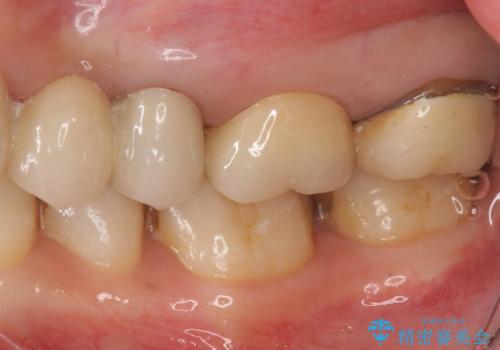

時々しみる奥歯 適合の悪いインレーからクラウンへのやり替え

- 左上の奥歯がたまにしみるとのことで来院。視診・レントゲン画像より明らかに劣化した不適な修復物を確認しました。

同じ材料で同じように修復し直してもまた同じような予後になることが予想されるため、適合の良いセラミックインレーでの治療を提案させていただきました。

しかし向かい合わせになる歯の咬みこみが強く、インレーでは破折してしまうリスクが高いと予想し、より強固なクラウンで修復することになりました。

向かい合わせの歯の咬みこみが強くインレーよりも強度の高いクラウンでの治療となりました。その中でも色が白くある程度の薄さでも耐久性を発揮するフルジルコニアクラウンでの修復を行いました。適合も良く色調もとてもなじんだため大変喜んでいただけました。